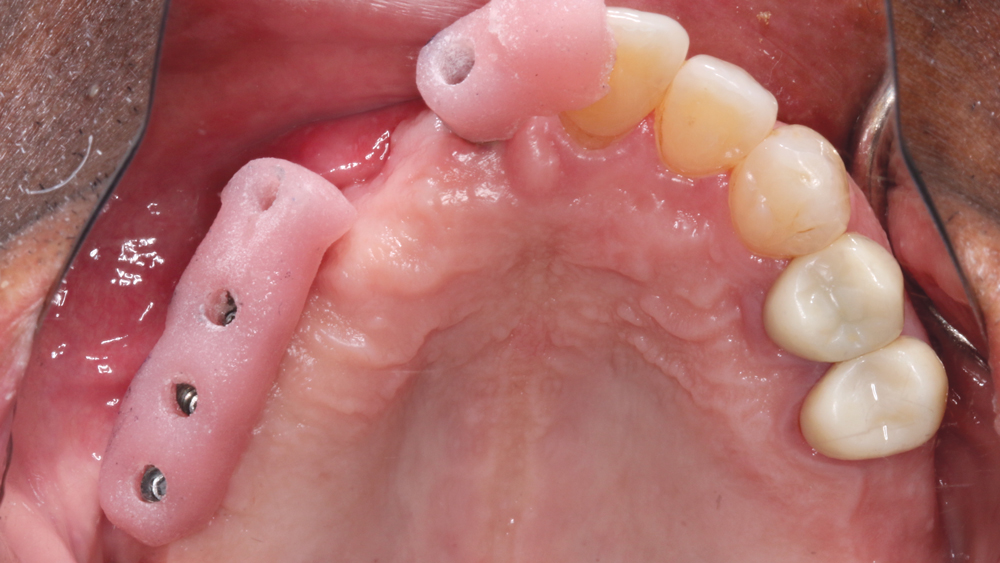

RESTORING THE CASE

Following integration of the implants for approximately four months, a final impression was made using Hahn Open-Tray Impression Copings (Glidewell Direct). The laboratory created a master cast and fabricated Inclusive® Titanium Custom Abutments for a cementable, implant-supported prosthesis. A screw-retained prosthesis was considered for this case, but because of the angulation of the seated implant fixtures, access holes would have exited through the facial aspect of the final prosthesis. Note that the patient is able to maintain the health of the tissue in the area of the restoration with a water pick, and the BruxZir Solid Zirconia material resists bacterial adhesion.

RESTORATIVE TECHNIQUES FOR ESTHETICS AND OCCLUSION

Esthetics and occlusion can be challenging in these types of cases. Restoring half an arch and trying to mirror the contralateral soft tissue and dentition with proper contours and shade requires patience and resolve. The lab provided a PMMA try-in prosthesis, which I evaluated with Weldon. The try-in allowed us to easily resolve any discrepancies with the prosthetic design and develop ideal occlusion. Once Weldon agreed on the esthetics, the PMMA provisional was returned to the lab and duplicated in BruxZir Solid Zirconia. This extra step eliminates excessive chairside adjustments upon seating of the final prosthesis.